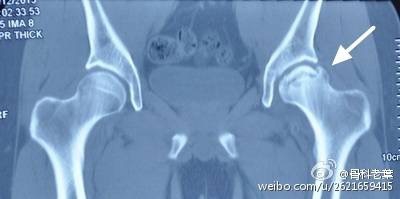

II期 病人有髋部症状,磁共振出现异常,X线片显示股骨头出现透光和硬化改变

III期 磁共振出现异常,X线片显示软骨下塌陷(新月征),股骨头内出现空洞,股骨头没有变扁

II期和III期的患者治疗方法相同,因为此时股骨头虽然还没有变形,暂时还不需要行人工关节置换术,但是股骨头已经出现空洞,随时股骨头就会塌陷变形,所以单纯的股骨头减压术是不能达到治疗效果的。这时就需要在股骨头减压的同时,植入一根支撑棒,顶住股骨头空洞区,防止股骨头在负重的情况下过早塌陷。其他治疗同之前相同,口服以上药物,定期复查,密切观察病情发展,尽量避免重体力劳动和爬山爬楼。